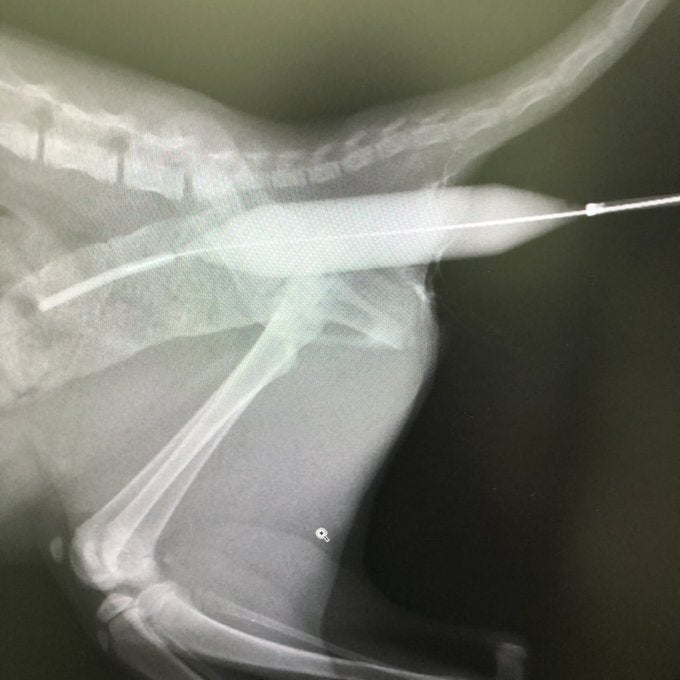

①は成長期の早いうちから実施したほうがよいと勧められたため、すでにバルーン拡張手術を2回実施しております。

7月17日(手術1回目)は7万7390円

7月26日(手術2回目)は器具代が入らなかったため、1万9000円でした。

拡張手術と毎日の投薬の結果、20㎜近くあった大腸は17㎜に収縮していることが判明しています。

5㎜の管を入れるのも困難だった肛門は、1.2㎜前後拡張を目標に少しずつ広がっています。

あんこの場合は、直腸と肛門がかろうじでつながっているので、まずは人工肛門の外科的手術の前に挿入したバルーンによる拡張手術に期待をかけています。